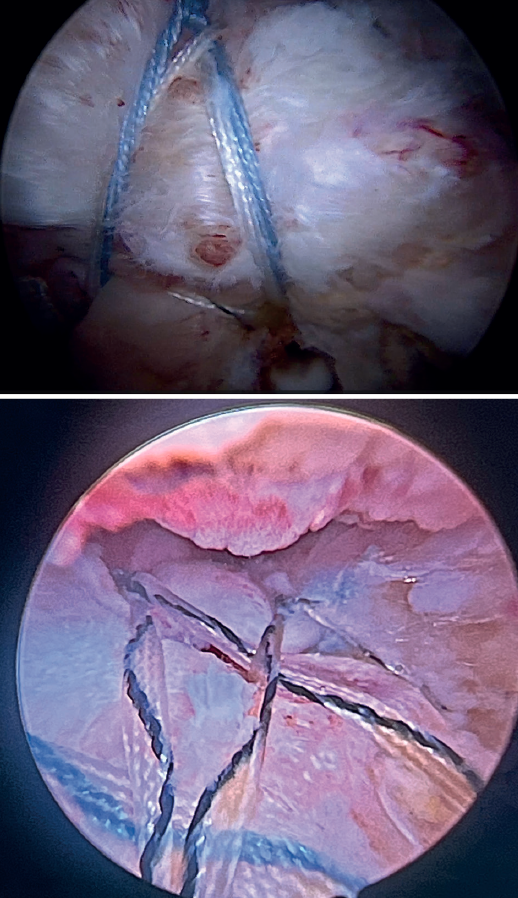

Tension-free repair of the supraspinatus tendon is then made, using the free thread left at the anchoring and taking advantage of the two sutures passed through and knotted to the proximal LPB fragment (Figures 8, 9 and 10).

The free suture remaining at the anchoring is passed through the anterolateral supraspinatus using a Scorpion® direct suture passer (Arthrex, Naples, FL, USA), as a sliding mattress suture over the implant.

One end of each of the sutures exiting the LPB is passed through the supraspinatus likewise using a Scorpion® direct suture passer (Arthrex, Naples, FL, USA). All the threads are left unknotted and are recovered through the anterior working portal so that they do not get in the way when working later on. Note that the two threads exiting the LPB and passing through the supraspinatus will not slide; it is therefore advisable to knot them and lower them later on with a knot pusher. This point allows repair of the anterior supraspinatus to be combined with fixation of the LPB in the anterolateral zone of the greater tuberosity.

A second anchorage loaded with two tapes is implanted at the same height as the first, but in a more posterior position. Again using direct suturing with mattress stitches, we repair the posterolateral part of the supraspinatus and even the anterior part of the infraspinatus, if necessary.

Having passed both the anterior and the posterior sutures, we proceed to knot, through the lateral portal with a working cannula, each of the sutures, starting posterior and ending anterior.

Finally, the anterolateral supraspinatus threads are used in combination with the posterolateral tapes to establish a more lateral double row with two direct anchorings that allow the threads to be threaded through two loops(Biocomposite SwiveLock® C 4.75 × 19.1 mm, Arthrex, Naples, FL, USA). This achieves a tension-free double row repair of the supraspinatus, covering the superior capsular repair made with the LPB (Figure 11).